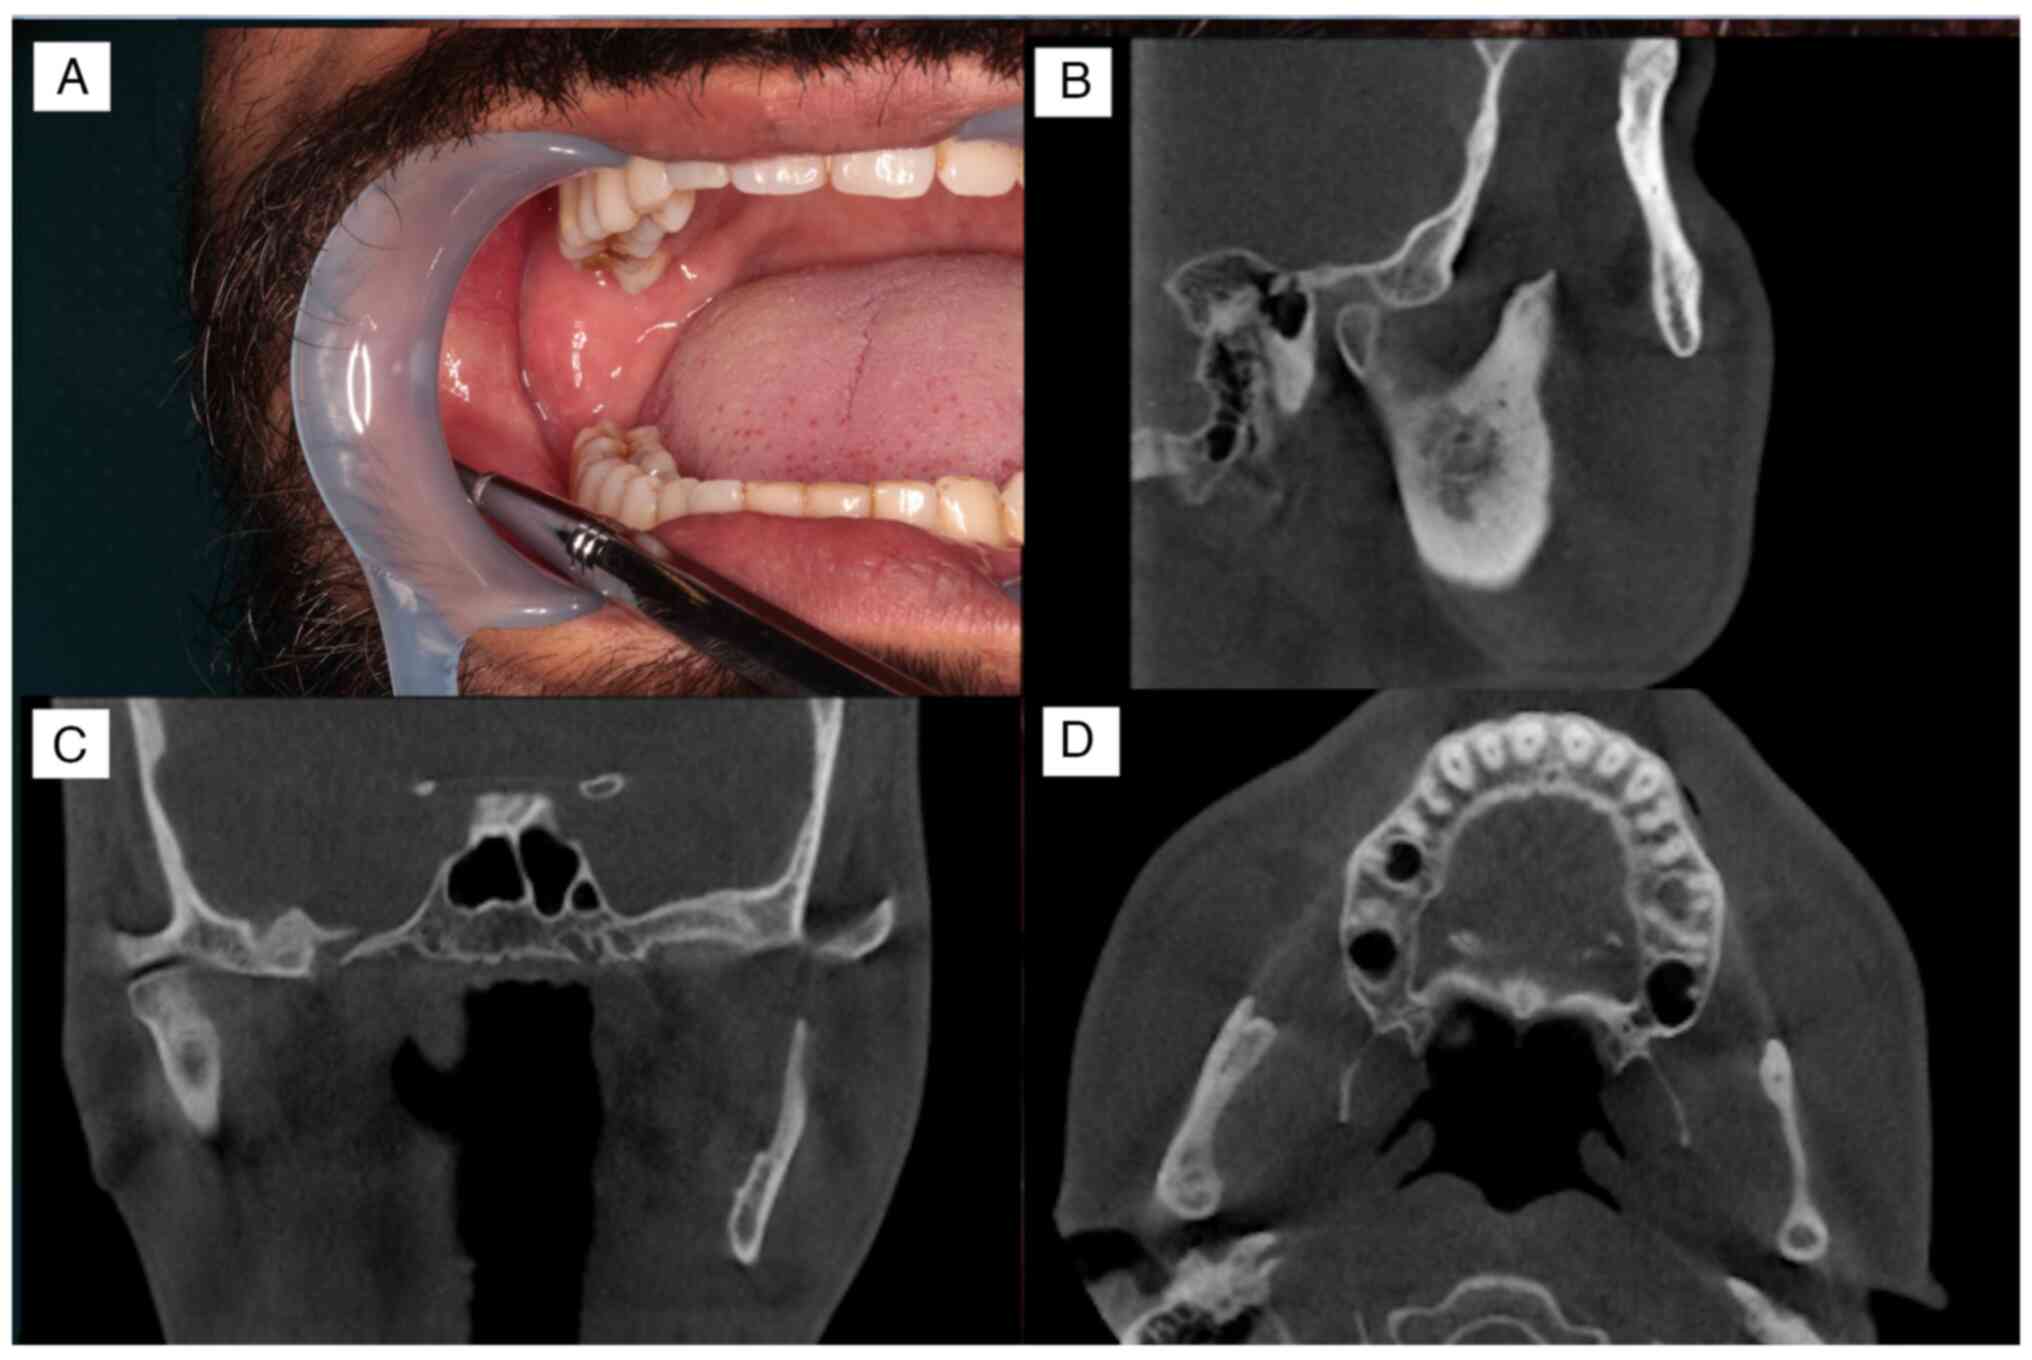

to the University of the Ryukyus Hospital, an intraoral examination

showed that the buccal gingiva corresponding to the lower right

wisdom tooth was depressed owing to previous surgery (Fig. 2A and B). Panoramic radiographic examination

showed an isolated cyst-like transmission in the base of the

condyle and the anterior margin of the right mandibular ramus

(Fig. 3). Cone-beam computed

tomography examination disclosed a cyst-like transmission image

measuring 13x12x6 mm in the base of the condyle. A suspected

residual cyst was detected in the anterior margin of the right

mandibular ramus. The cysts were not connected and both were not in

contact with the inferior alveolar nerve (Fig. 4A-C). The long-term, continuous use